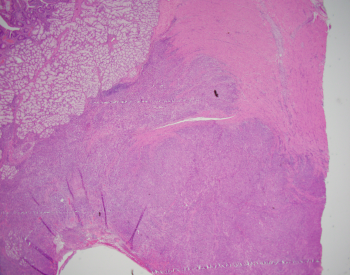

Case History:

A 40 y/o euthyroid female and a 3 cm left-sided thyroid nodule incidentally found.